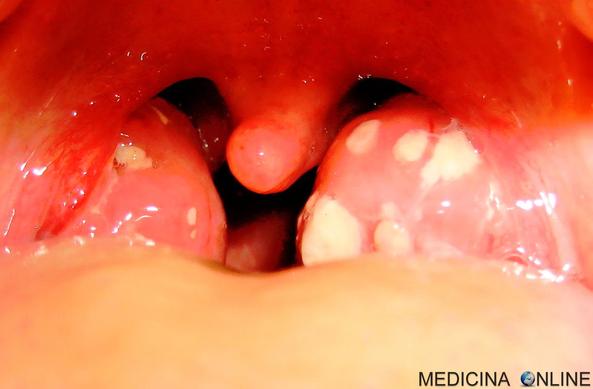

🔵 Placche in gola e sulle tonsille: cause, rimedi, sono contagiose, quanto durano?

👉 Leggi l’articolo: https://medicinaonline.co/2022/12/29/placche-in-gola/